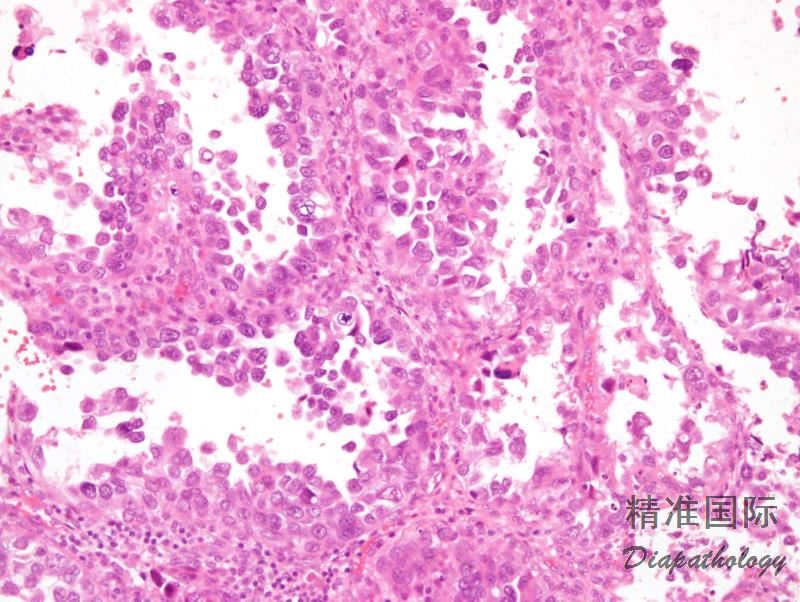

由胞浆透亮或嗜酸性,最少局部具有高级别核的多角形或鞋钉样细胞呈实性、乳头状或管状排列的肿瘤,属于 II 型子宫内膜癌。

肿瘤呈实性、乳头状、管状和囊状结构,各种结构比例变化很大,可以以一种结构为主;

实性结构常由大量透明细胞混杂嗜酸性细胞组成,而乳头状、管状和囊状结构主要由鞋钉样细胞组成(核大,突出于腺腔),其间散在透明和嗜酸性细胞;囊状结构常衬覆扁平细胞;

细胞异型性、多形性不一致,但最少有部分细胞为高级别核,表现为细胞核大,明显多形性,多数病例核分裂像多见,并可见病理性核分裂像;